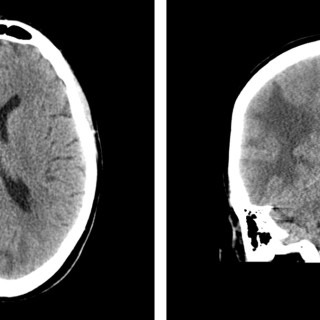

Magesmerter hos barn er en hyppig årsak til henvisning til barnemedisinsk og kirurgisk spesialisthelsetjeneste. Akutt appendisitt, obstipasjon og gastroøsofageal refluks er blant de vanligste diagnosene. Ofte kan barn ha diffuse symptomer, og selv om «det vanligste er det vanligste», er det viktig å være oppmerksom på symptomer som tyder på alvorlig, underliggende patologi. Tett samarbeid mellom fastlege, barnelege, barnekirurg og radiolog kan være viktig for å komme til målet. En jente tidlig i tenårene hadde vært plaget av «treg mage» siden småbarnsalder og hadde gjennom de siste fem årene...